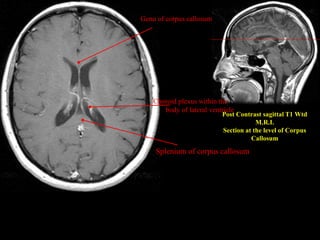

Post Contrast sagittal T1 Wtd

M.R.I.

Section at the level of Corpus

Callosum

Genu of corpus callosum

Splenium of corpus callosum

Choroid plexus within the

body of lateral ventricle

Post Contrast sagittalT1 Wtd M.R.I. Section at the level of Corpus Callosum Genu of corpus callosum Splenium of corpus callosum Choroid plexus within the body of lateral ventricle

• 43.